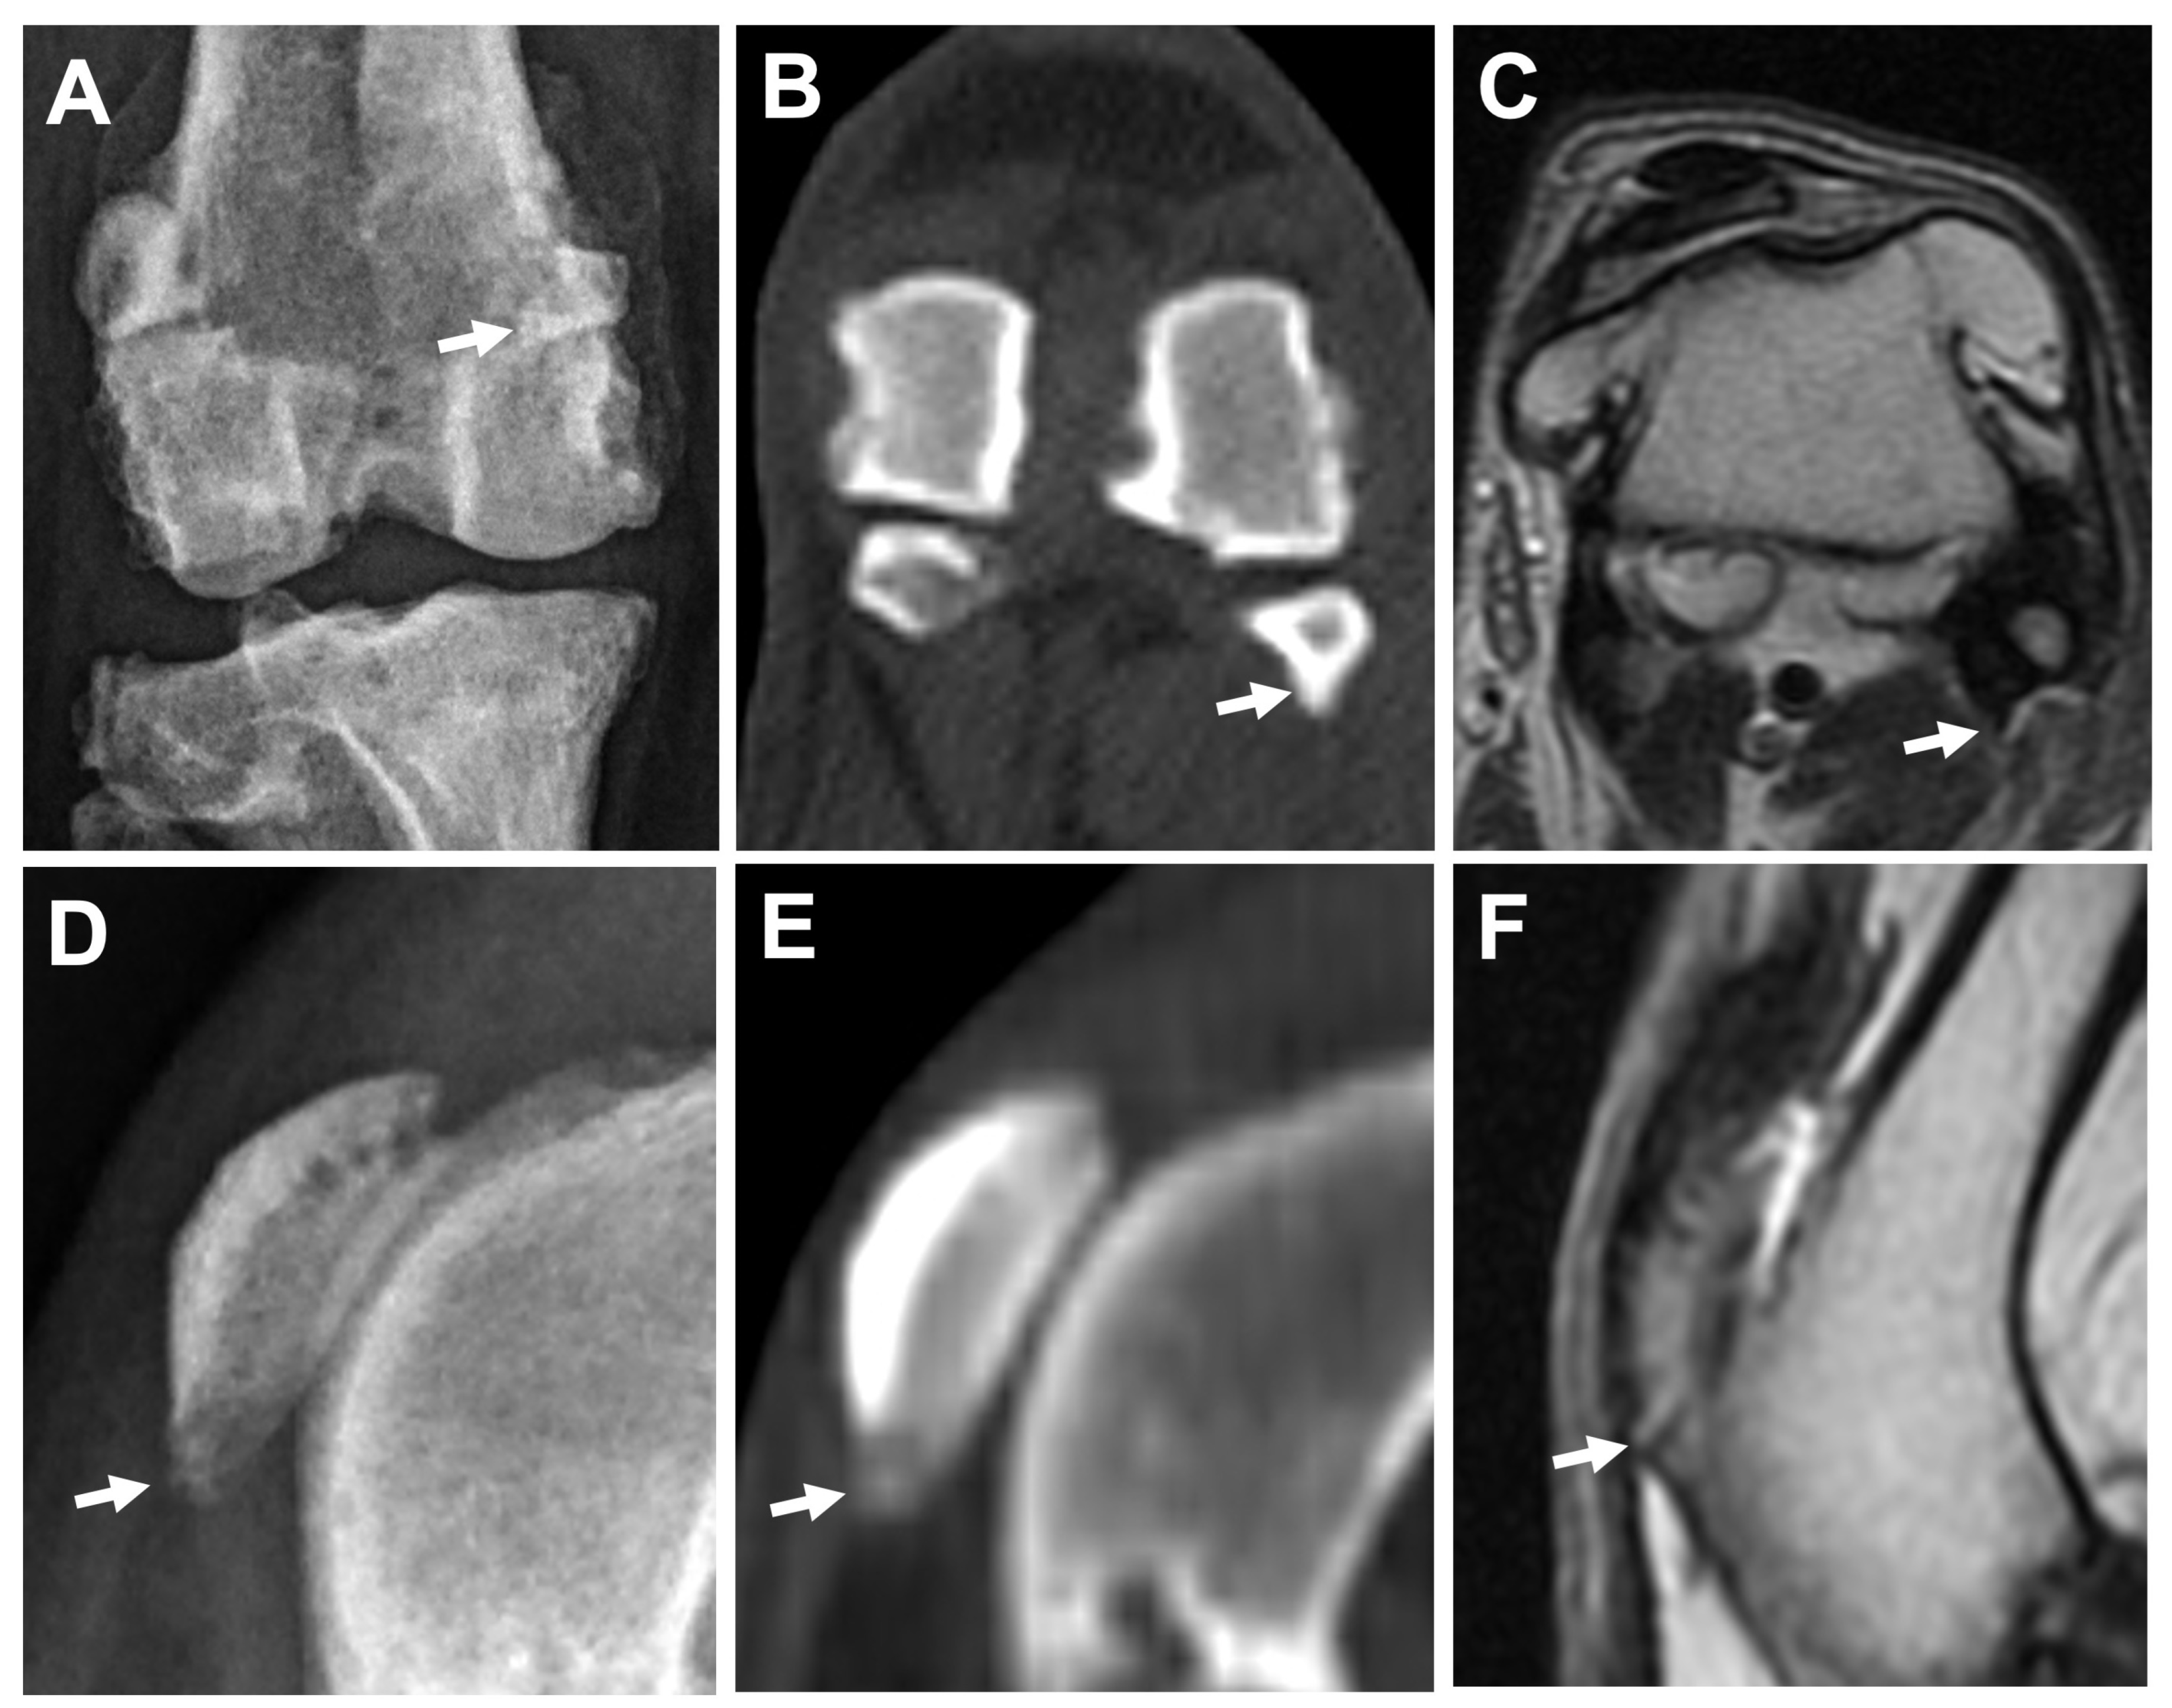

3.2.1. Osteophytes/Enthesophytes

3.2.2. Ligament/Tendon Lesions

3.2.3. Synovial Effusion and Membrane Thickening

3.2.4. Subchondral Bone Lesions

3.2.5. Meniscal and Cartilage Lesions